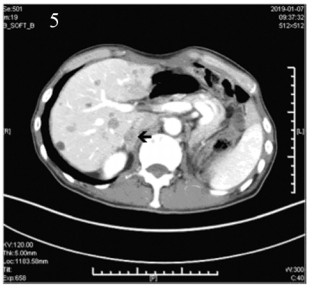

2018年10月22日、2018年11月12日开始行第一、二疗程免疫联合抗血管生成治疗:帕博利珠单抗(100 mg, d1)+安罗替尼(12 mg, qd, d1~14)q3w。治疗前检查甲状腺、肝肾功能正常,无免疫性基础疾病。治疗不良反应:骨关节酸痛,余无明显不适。两疗程治疗后进行评估,2018年11月29日LDH 272 u/L,病情评估疾病稳定(stable disease, SD)。2018年12月3日、2018年12月24日行第三、四疗程免疫加抗血管生成治疗后行疗效评估,2019年1月7日上腹部增强CT示右侧肾上腺转移性病灶,见图 5。2019年1月8日LDH 356 u/L。患者出现右侧肾上腺新发转移,肝脏病灶较前增多,病情评估PD。后患者因达到帕博利珠单抗及安罗替尼赠药,要求继续原方案治疗,2019年1月14日、2019年2月3日行第五、六疗程免疫加抗血管生成治疗,剂量同前。治疗后再次评估,2019年2月21日疗效评估PD,此时LDH 698 u/L,治疗过程中患者有反酸不适。